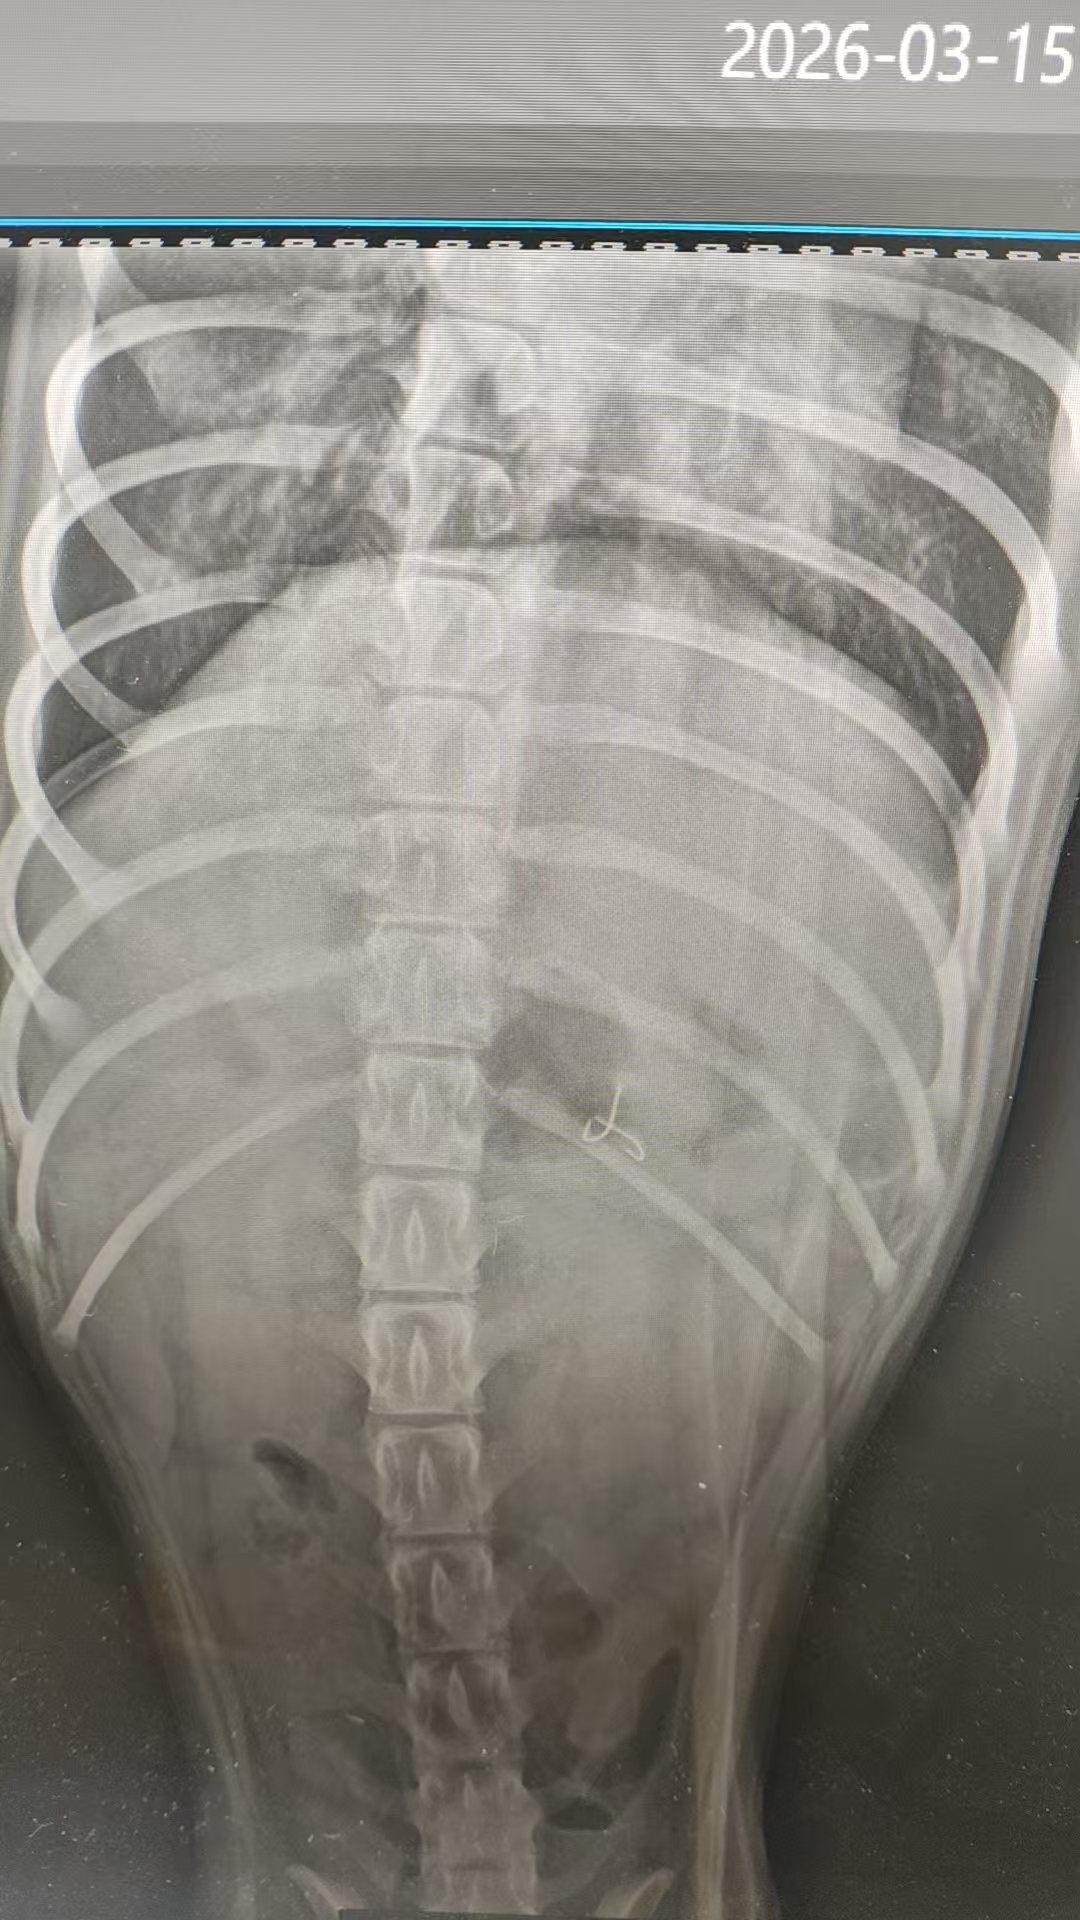

【病例概况】• 患宠:1岁雄性泰迪,体重3.24kg,日常活泼好动• 主诉:最近出现咳嗽,并且有痰,今天早上开始精神食欲不是很好• 初诊时间:2026年3月一、接诊• 临床症状:精神萎靡,呼吸声沉重,鼻梁边有分泌物• 实验室检查:DR,犬呼吸道七联• 检查结果:支原体阳性,DR显示心脏大小异常,建议...